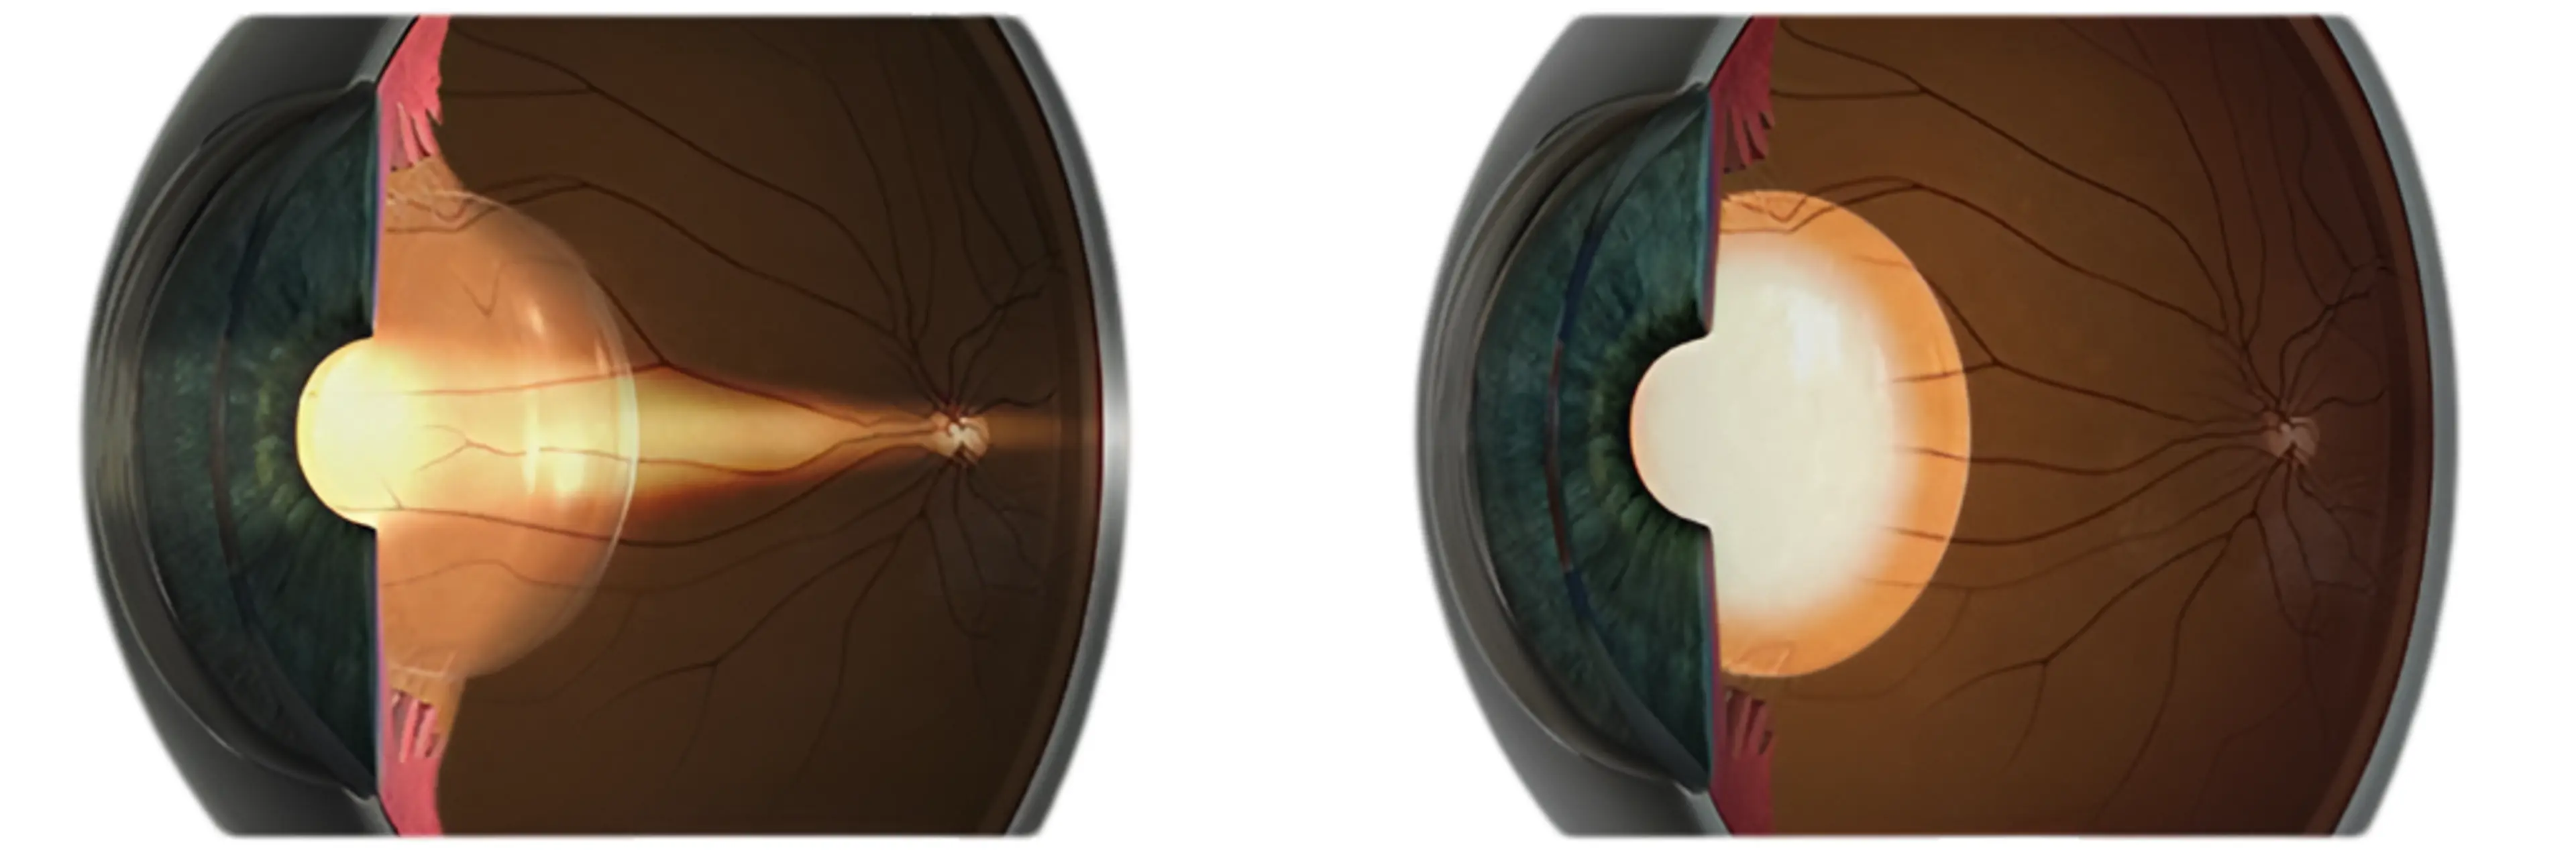

白内障是一种常见的眼部疾病,全球范围内影响数百万人,尤其好发于老年人群。该疾病由眼睛天然晶状体发生混浊导致,会造成视力模糊,严重影响阅读、驾驶及人脸识别等日常活动。白内障发展进程缓慢,早期症状可能不明显,但随着病情进展将显著降低患者生活质量。值得庆幸的是,通过现代眼科手术可有效治疗白内障。

白内障和老花眼都可能引发视力模糊等相似症状,但这是两种完全不同的眼部疾病。老花眼通常始于40岁左右,是由于眼睛晶状体逐渐失去弹性,导致近距离视物困难。而白内障则是晶状体发生混浊,影响远、中、近全程视力。

白内障唯一有效的治疗方式是白内障手术,即摘除混浊的天然晶状体并置换为人工晶体(IOL)。作为全球最安全且常规的眼科手术之一,白内障手术成功率极高。当白内障开始影响日常生活且眼镜矫正无效时,通常建议进行手术治疗。